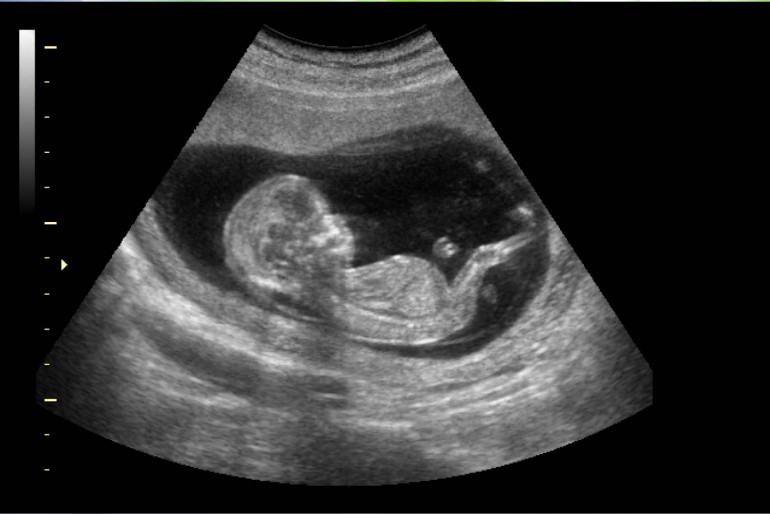

P3: Baules (projectes) Feu un comentari / I3 Informació Setmanal Portada / Per admin Us tornem a demanar un altre cop la vostra col·laboració per tal de treballar la nostra primera baula (projecte) sobre els cocodrils i els pingüins. Necessitaríem radiografies d’alguna part del cos i ecografies de nadons. Moltes gràcies. Mestres de P3